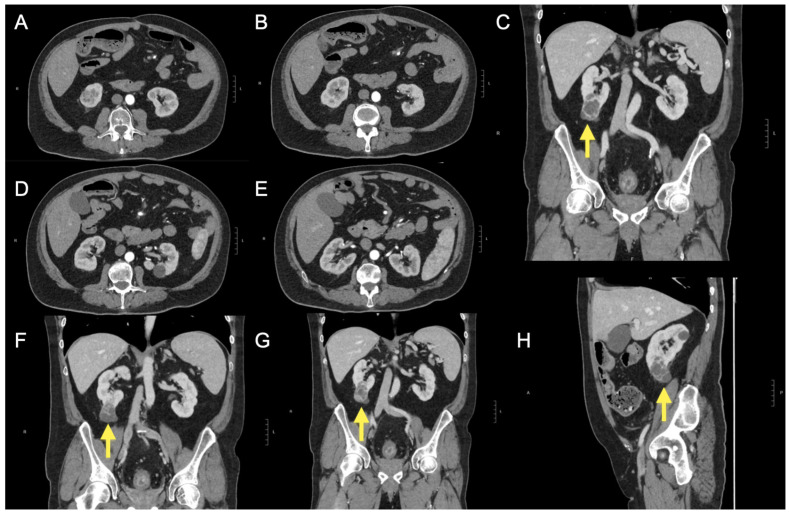

Background/Objectives: Renal cell cancer is a rare occurrence in patients with ulcerative colitis (UC), with no clearly demonstrated association between UC and an increased risk of renal malignancies. In this article, a case report concerning this relationship is presented. Methods: Our research group presented a case of clear cell renal carcinoma in a 56-year-old male with UC who had previously undergone ileorectal anastomosis and subtotal colectomy. Results: The patient developed a complex renal cyst that progressed to malignancy within one year while on immunosuppressive therapy with infliximab and then filgotinib. Previous ultrasound examinations of the kidney highlighted only simple cysts in the contralateral kidney in previous years. The neoplasm was promptly examined using contrast-enhanced ultrasound, confirming the diagnosis of a Bosniak IV cyst, which was corroborated by a subsequent computed tomography study. Conclusions: The patient underwent a nephrectomy and is currently scheduled for therapy with vedolizumab. Given the increasing use of biologics and small molecules in UC management, periodic ultrasound screening may be a valuable tool for the long-term monitoring of these patients.